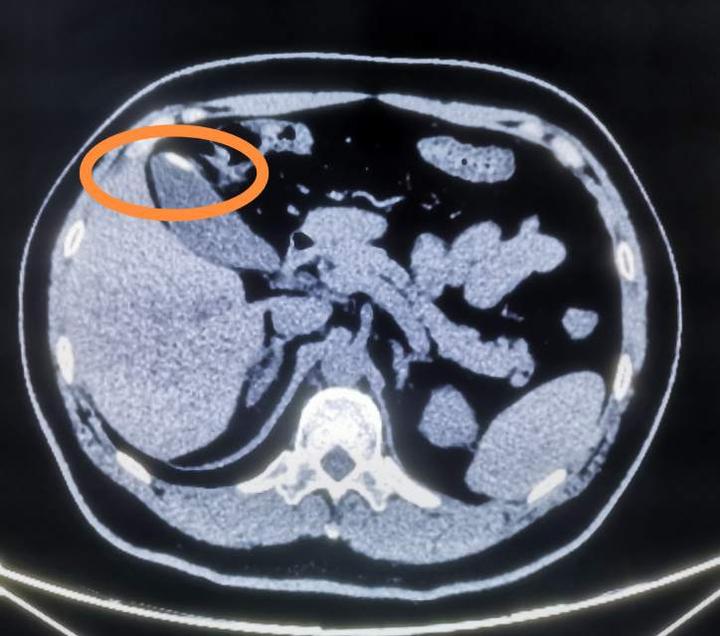

隐匿癌的瓷化胆囊一例